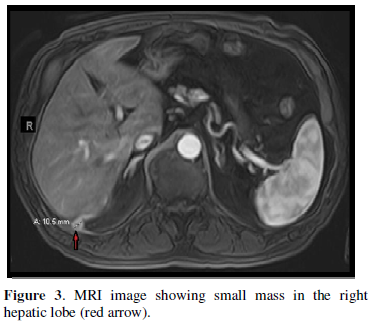

In May 2019, the patient’s primary care physician obtained a CT scan of the abdomen and pelvis without contrast due to intermittent dull and mild right upper quadrant abdominal pain. Per the CT scan report there was an unidentified liver lesion measuring 1.3 x 1.5 cm. Thus, the patient was referred to an oncologist in July 2019 due to a concern of hepatocellular carcinoma. The patient’s oncologist initiated work up which resulted in an alpha fetoprotein (AFP) of 4.7 nanogram per milliliter (ng/ml), that was within normal limits, and a negative acute viral hepatitis panel. MRI with and without contrast of the liver showed an area of abnormal signal and enhancement within the inferior medial aspect of the right lobe of the liver with ring enhancement measuring 1.5 x 1.0 centimeters (cm) (Figure 3).